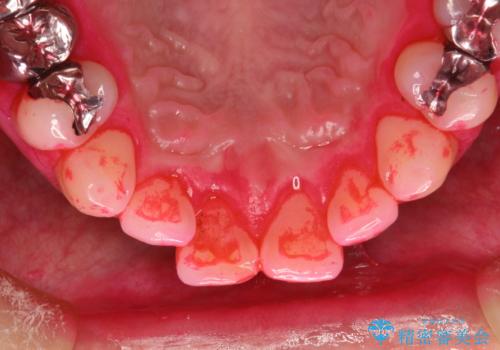

- 歯科でのクリーニングがかなり久しぶりで口臭も気になるとのことで来院されました。PMTCの60分コースで、染め出し・ブラッシング指導・クリーニングを行いました。

適切な歯磨き方法を習得するには、染め出しを行い、磨き残しを把握していくことがポイントです。

磨けているよう、磨いているつもりでも、汚れが残ってしまうと、毎日の歯磨き時間が無駄になってしまうこともあります。効率的に歯磨きを行い、磨き残しを減らせるように、歯科衛生士による専門的な指導を行います。